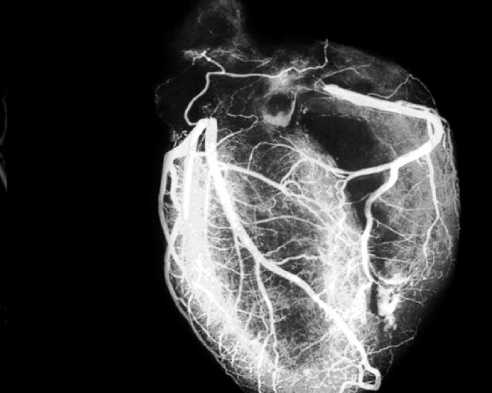

Наиболее распространенным методом оценки состояния сосудов сердца является селективная катетерная коронарография. Метод заключается в пункции под местной анестезией крупной артерии (чаще всего, бедренной или лучевой), подведении специально сформированного катетера к устью коронарной артерии и селективного болюсного введения контрастирующего вещества последовательно в левую, а затем в правую коронарную артерии.

Рис. 9.37. Левая коронарная артерия. Правая косая проекция.

Здесь и на рис. 9.38—9.46:

1 — левая коронарная артерия; 2 — проксимальная треть передней нисходящей артерии; 3 — первая диагональная ветвь передней нисходящей артерии; 4 — дистальная часть передней нисходящей артерии; 5 — септальная ветвь передней нисходящей артерии; 6 — проксимальная часть огибающей артерии; 7 — первая маргинальная ветвь огибающей артерии; 8 — промежуточная артерия; 9 — дистальная часть огибающей артерии; 10 — проксимальная часть правой коронарной артерии; 11 — ветвь синусного узла правой коронарной артерии; 12 — ветвь острого края правой коронарной артерии; 13 — бифуркация правой коронарной артерии; 14 — правая левожелудочковая ветвь правой коронарной артерии; 15 — задняя нисходящая ветвь правой коронарной артерии.

Фиксация изображения коронарных артерий производится последовательно в нескольких плоскостях.

На рис. 9.37—9.41 изображены левая и правая коронарные артерии и их ветви при равномерном типе коронарного кровообращения в обычной последовательности проекций.

На следующих рисунках представлены два типа коронарного кровообращения — правый и левый и характеризующиеся неравномерным развитием правой коронарной и огибающей (ветвь левой коронарной артерии) артерий. При левом типе отмечается выраженная периферия огибающей артерии при значительной гипоплазии правой коронарной артерии. При правом типе чаще всего хорошо развита маргинальная ветвь и гипоплазирована основная ветвь огибающей артерии. Периферия правой коронарной и, в особенности, правая левожелудочковая ветвь значительно выражены и превосходят огибающую по размерам зоны кровоснабжения.